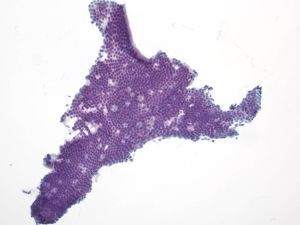

Acinar Cell Carcinoma – PAN2-036

Key Cytological Features: Acinar Cell Carcinoma

- Solid-cellular smear pattern of monomorphic cells

- Cellular clusters of various sizes and single cells (loss of organoid "grape-like Clustering of benign acinar tissue)

- Stripped naked nuclei; +/- loose cytoplasmic granules (best noted on Hand E stain)

- May be disarmingly bland, with a polygonal cell shape and low N:C

- Coarse chromatin usually with prominent nucleoli, but not always granular cytoplasm, variably prominent